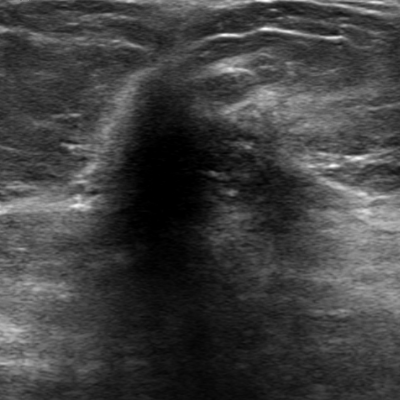

Refer to caption

Figure 1: A malignant lesion in breast ultrasound

In the clinical workflow of breast ultrasound imaging, radiologists often report the sizes of breast lesions, describe the lesions according to BI-RADS lexicon[6] and estimate the final BI-RADS score. An accurate delineation of breast lesion can help radiologists to describe margin, shape and posterior features. However, manual segmentation of breast lesions is time-consuming and tedious. The segmentation also varies from one reader to another. Therefore, the automated segmentation can play a key role in facilitating the reporting of the diagnosis. In terms of detection and diagnosis, computers can also assist radiologists to make decisions that improve the effectiveness of ultrasound reading. For example, computer techniques[7, 8, 9, 10, 11, 12, 13, 14] have been proposed to delineate the contour of lesions or directly detect or diagnose breast lesions. Most of these computer-aided diagnoses or detections include a module of segmentation. Therefore, it is important to develop a robust and accurate segmentation method.

Breast lesion segmentation is very challenging, especially when there is the presence of noise, the ill-defined edges, irregular shapes, and different posterior behaviors of lesions. As Fig. 1 shows, there is strong shadowing in the posterior and upper region, the lesion boundary is fuzzy and not clear. Therefore, there is a risk that segmentation algorithms fail, causing oversegmentation.